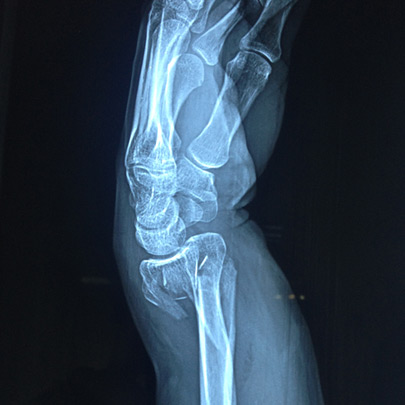

Fracturas y luxaciones

Cirugía de codo